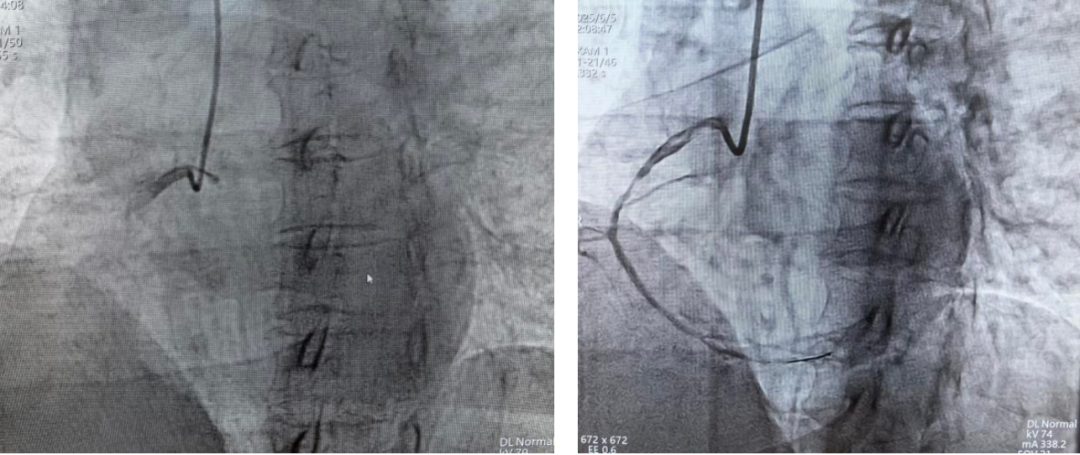

患者被送进标准化心血管导管室,韦波凭借丰富的临床经验与娴熟技术,迅速进行冠状动脉造影,发现患者右冠状动脉(RCA)近中段完全闭塞。术中,韦波成功将导丝通过闭塞病变区域,并使用2.0mm球囊扩张闭塞部位,顺利打通堵塞血管,使血管再通,手术历时近一个小时,成功帮助患者恢复心肌供血。鉴于患者自身以及术中情况,医疗队评估其暂不植入支架,待病情稳定后择期实施。

PCI术后,梗塞的右冠状动脉已恢复正常血流供应